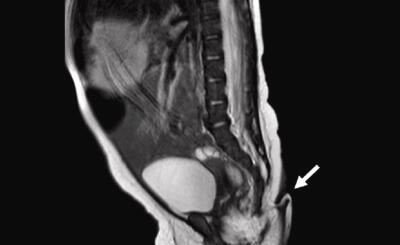

Cuando tenía 22 años, Sulemana Abdul Samed fue diagnosticado con el síndrome de Marfan, una condición que afecta la columna vertebral y a otros órganos y extremidades del cuerpo humano.